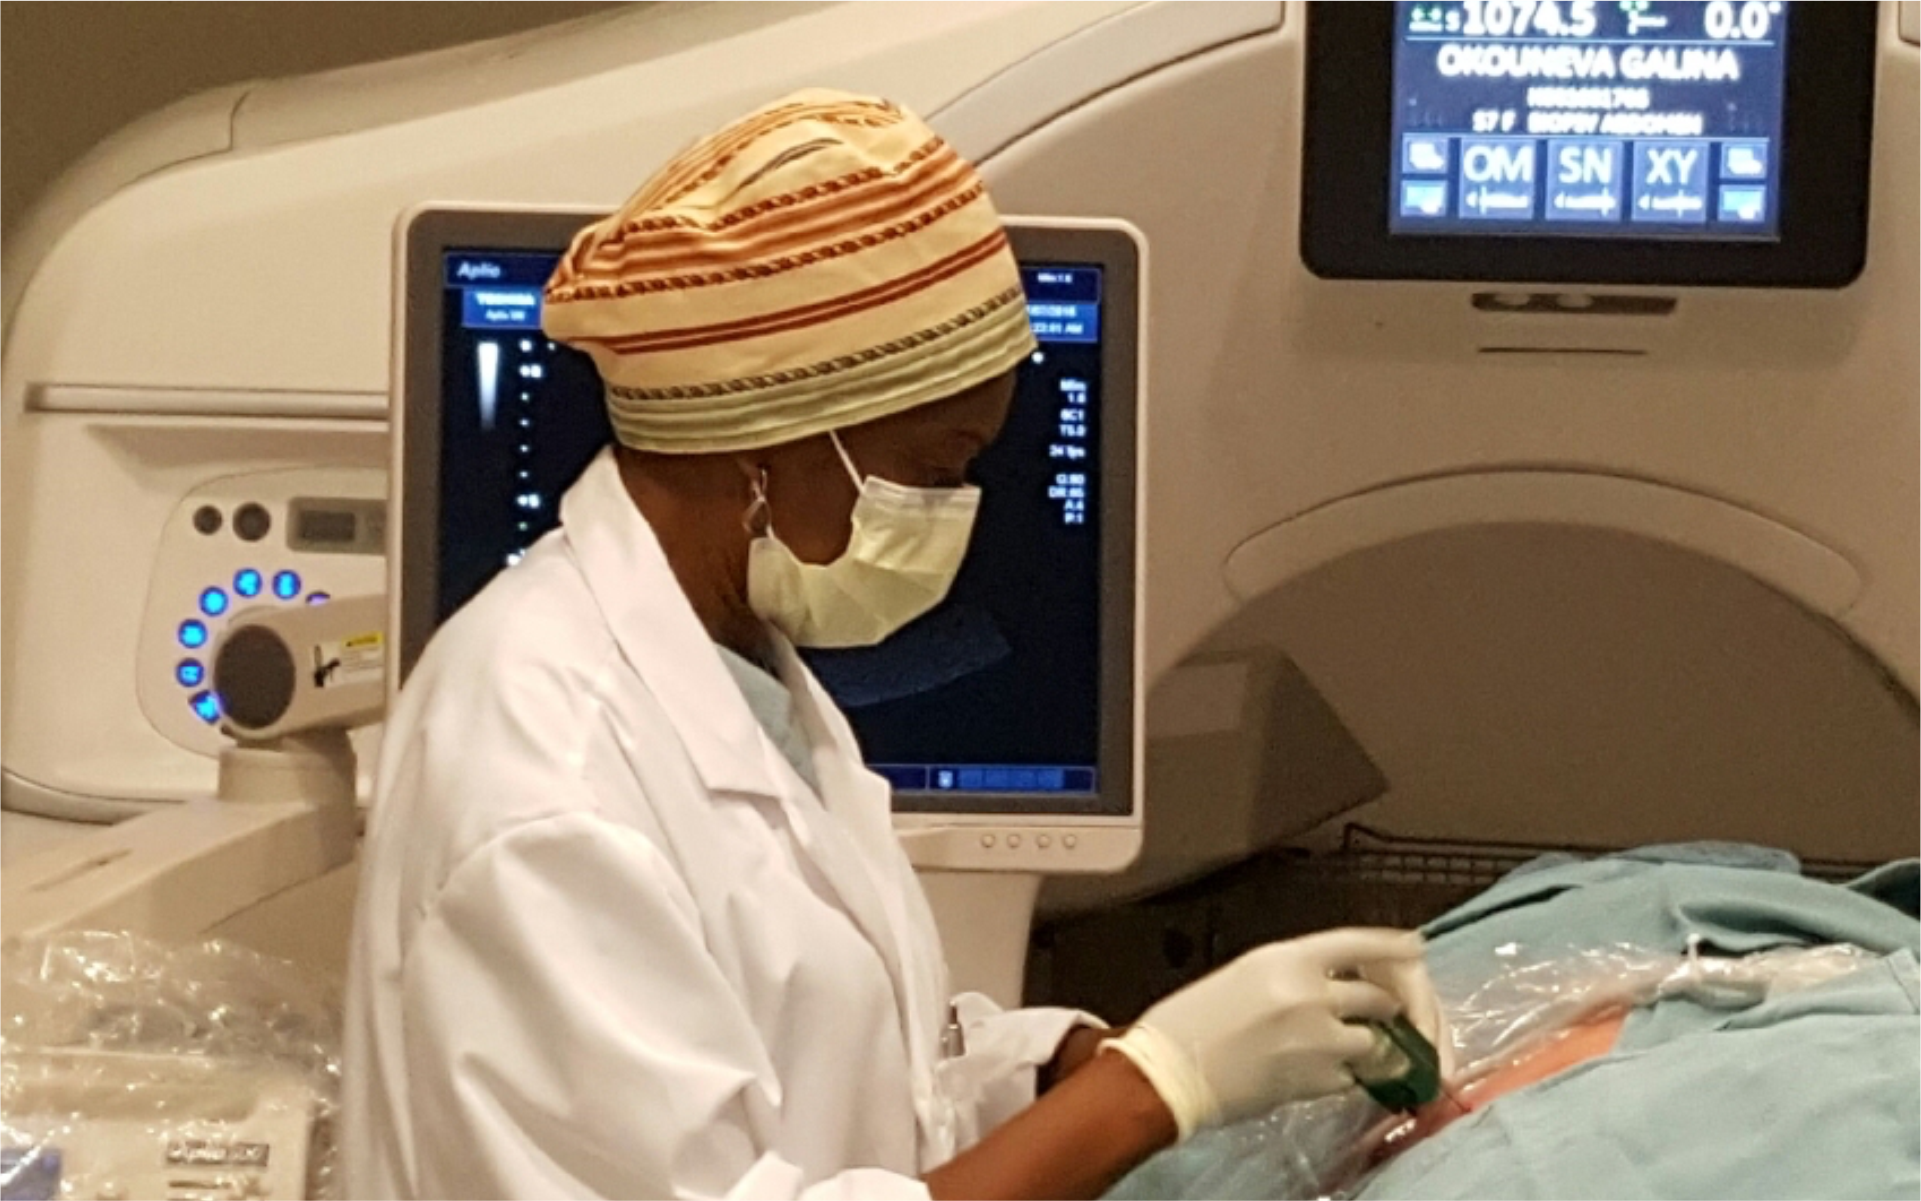

Interventional Radiology Service (IR)

Interventional radiology, is a radiology specialty which provides minimally invasive image-guided diagnosis and treatment… ...